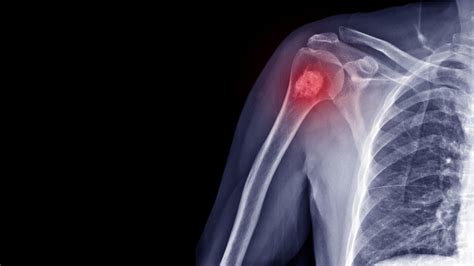

Diagnosis of Cancer en los Huesos

Diagnosing cancer en los huesos involves a combination of medical history, physical examination, and diagnostic tests. The diagnostic process typically includes:

• Imaging Tests: X-rays, CT scans, MRI scans, and bone scans can help identify bone abnormalities and determine the extent of the cancer.